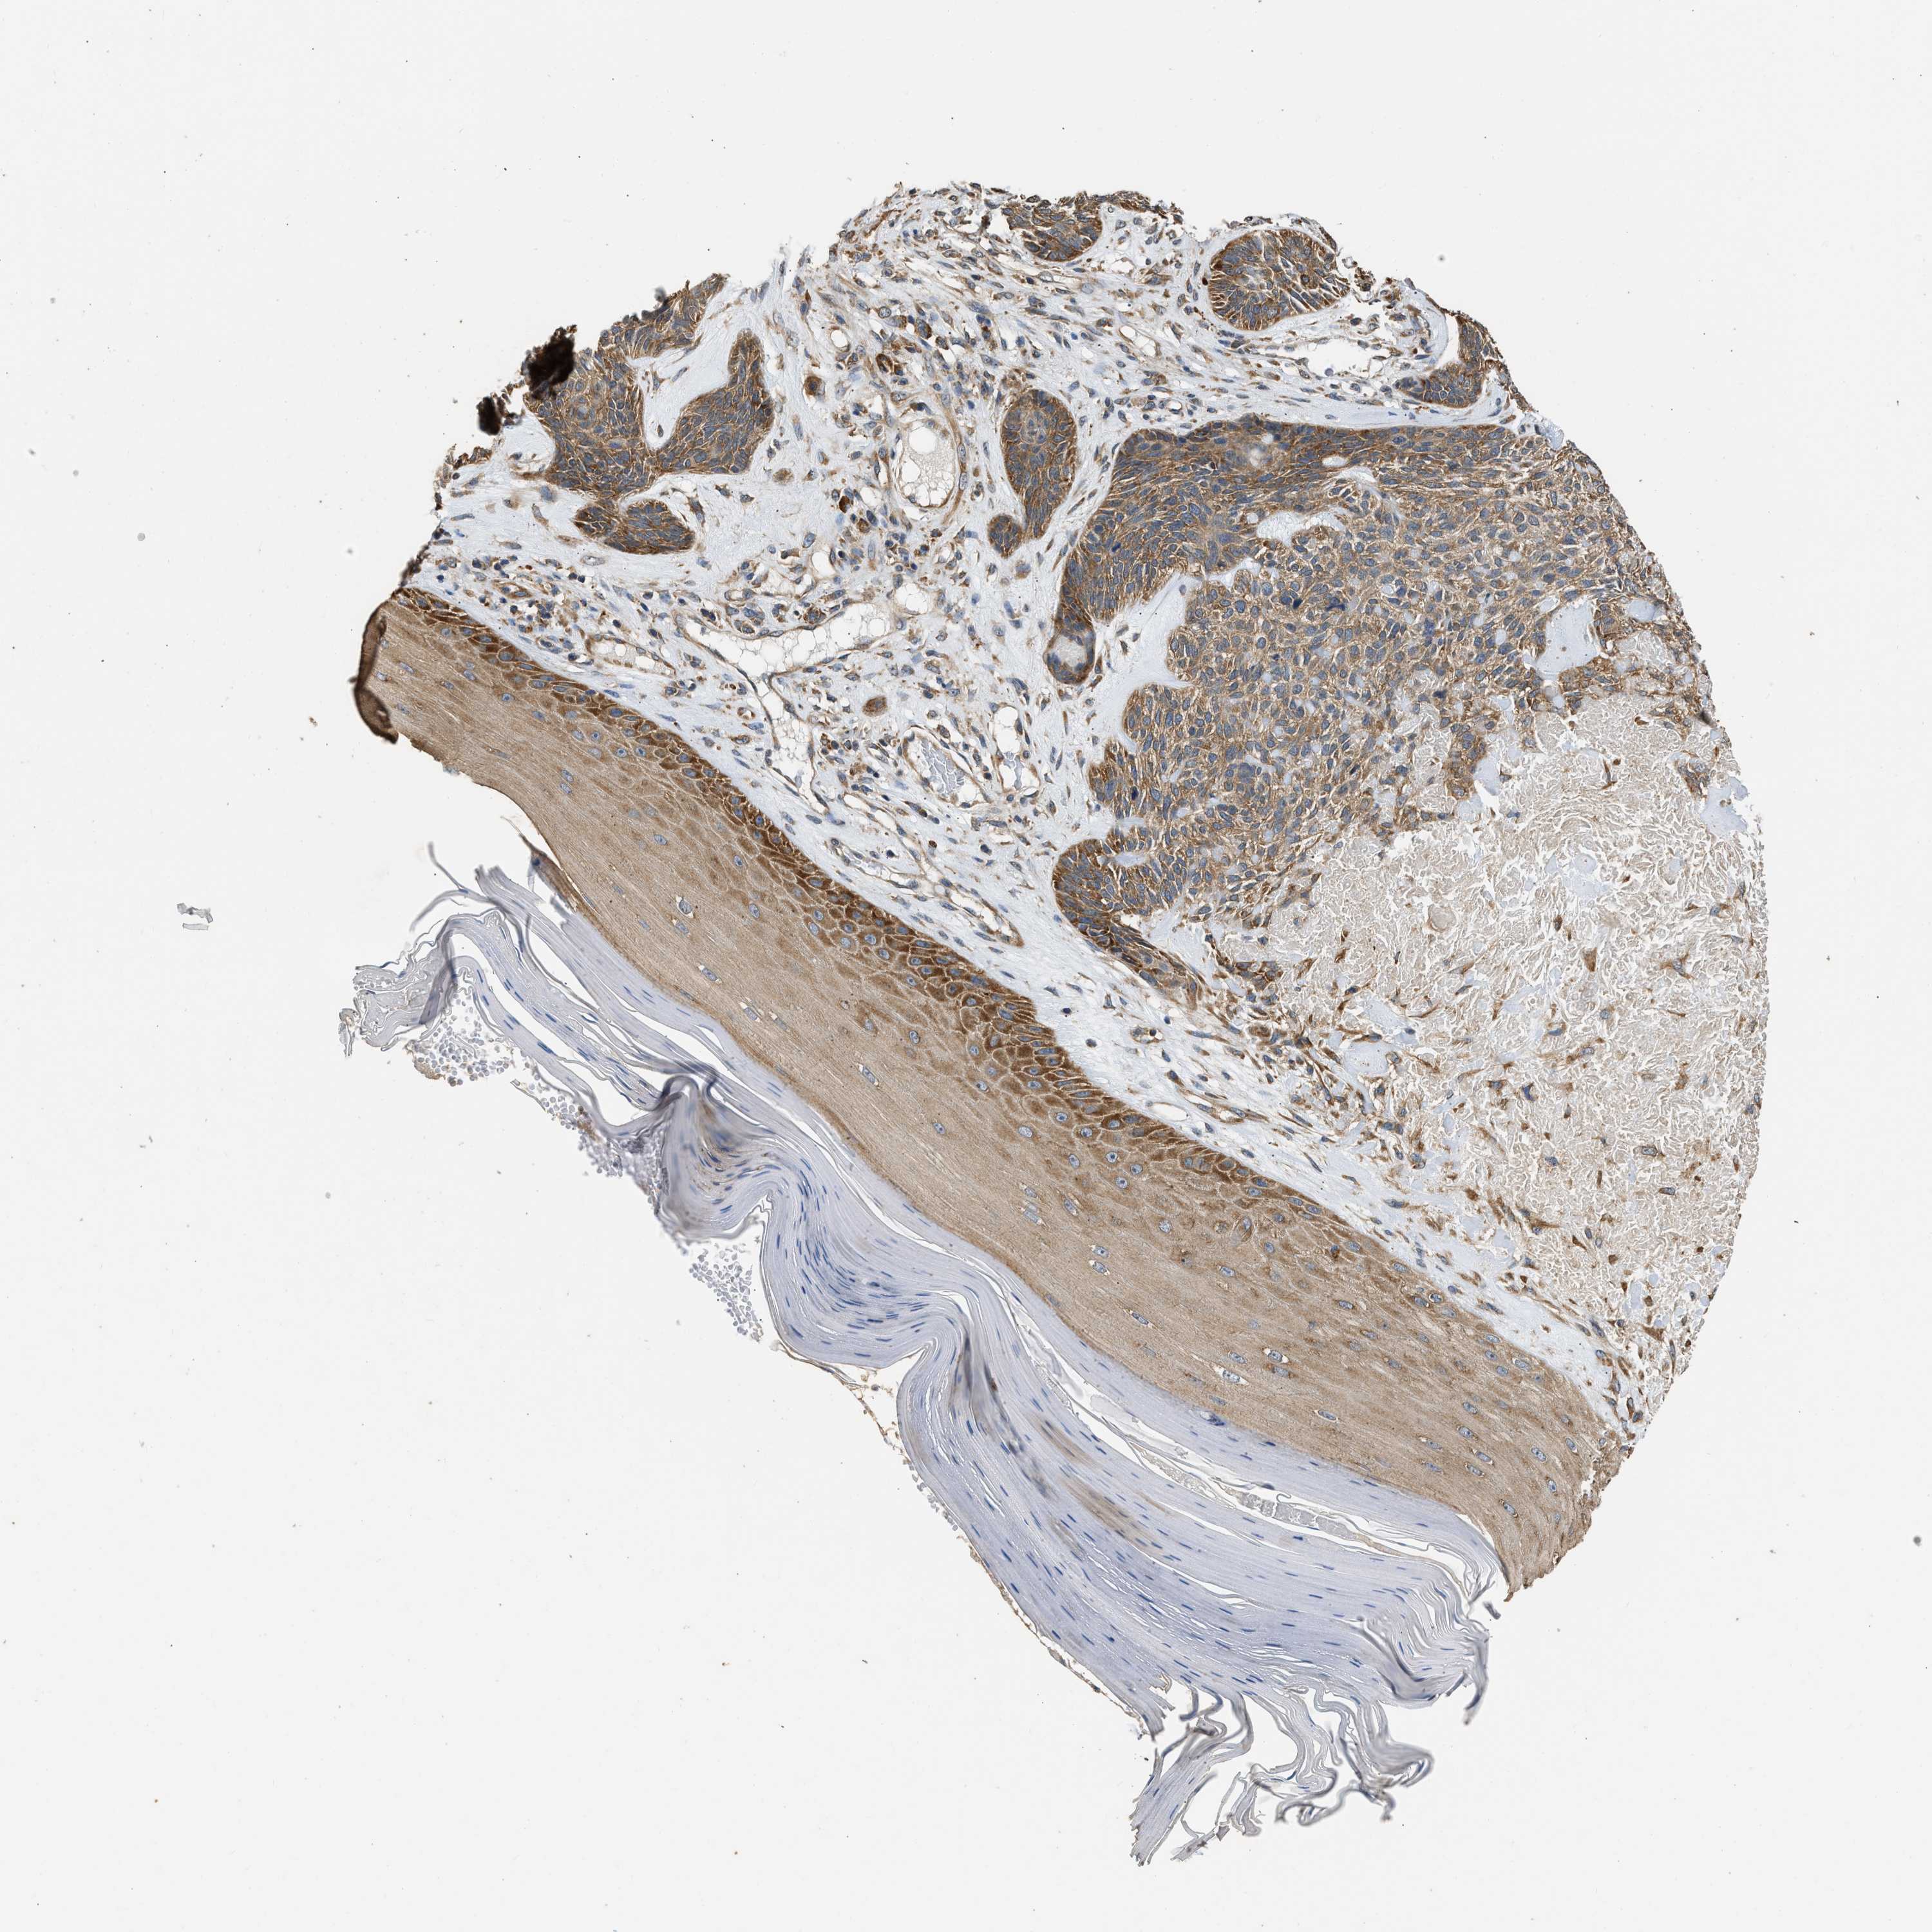

SKIN CANCER - Protein expressioni

A mouse-over function shows sample information and annotation data. Click on an image to view it in a full screen mode. Samples can be filtered based on level of antibody staining by selecting one or several of the following categories: high, medium, low and not detected. The assay and annotation is described here.

Antibody stainingi

Antibody staining in the annotated cell types in the current human tissue is reported as not detected, low, medium, or high, based on conventional immunohistochemistry profiling in selected tissues. This score is based on the combination of the staining intensity and fraction of stained cells.

Each image is clickable and will lead to virtual microscopy that enables deeper exploration of all samples and also displays staining intensity scores, fraction scores and subcellular localization as well as patient and tissue information for each sample.

Antibody HPA017887

Staining

Medium

Intensity

Moderate

Quantity

75%-25%

Location

Cytoplasmic/membranous

Basal cell carcinoma